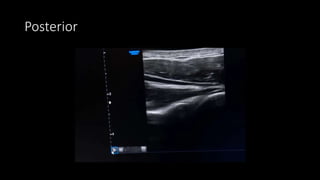

Posterior Scanning Protocol

• Patient arm in neutral resting

adduction, palm supinated on the

lap

• Orient transducer axial to view the

posterior glenohumeral joint and

posterior labrum

• Assess supraspinatus muscle

(above the scapular spine)

• Assess infraspinatus and teres

minor muscles (below the scapular

spine)

• Follow course to its insertion into

the greater tuberosity

• Examine both muscles in long and

short axes to determine difference

in muscle bulk, or find fatty

atrophy.

• Compare right and left – to

determine atrophy